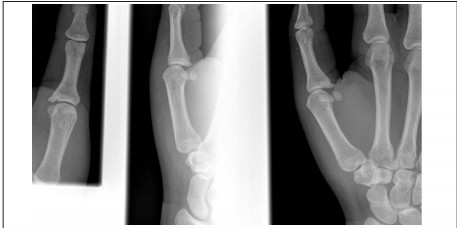

Tuft fractures are the most common distal phalanx injury. By definition, a tuft fracture is a comminuted fracture of the head and tuberosity of the distal phalanx, usually without any displacement or angulation. (See Figure 7.) Due to proximity of the fingernail dorsally, and septa volarly, these fractures are generally stable. They are commonly associated with lacerations, crush forces, and subungual hematomas. If a tuft fracture is open, thorough irrigation with debridement of devitalized tissue is necessary. The use of prophylactic antibiotics for open tuft fractures is still a subject of controversy.19 However, if any doubt exists about the severity of injury or infection risk, it is prudent to provide antibiotic prophylaxis.

Figure 7. Radiograph of Tuft Fracture

Finger dislocations are relatively common pediatric injuries. The most common type is dorsal dislocation at the proximal interphalangeal joint (PIP), with volar PIP dislocations being less common but equally important.23 (See Figure 10.) It is vital to distinguish between dorsal and volar PIP dislocations, since their treatments are different. The more prevalent dorsal dislocations occur with hyperextension and involve the middle phalanx moving dorsally in relation to the proximal phalanx.22 This motion causes a disruption in the volar plate (which stabilizes the joint from the palmar surface). Volar plate rupture may or may not involve an avulsion fracture, which would be seen best on lateral X-ray. Reduction of the dorsal dislocation includes the following: After the provision of analgesia via digital block, longitudinal traction is placed on the middle phalanx, followed by volar pressure on the middle phalanx and dorsal counter pressure on the proximal phalanx. After reduction, a finger splint should be placed. The finger should be splinted with the affected joint in a 30-degree flexed position. Splinting in the flexed position fosters improved healing of the volar plate.22 A volar dislocation, by contrast, involves injury to the central extensor slip. Pain on resisted extension is a cardinal sign of this injury.23 Since volar dislocations involve the disruption of dorsal structures, they should be splinted in full extension to bring the disrupted segments together. In some cases, a dislocation may reduce spontaneously, or the athlete may reduce it before arrival. If this occurs, the following physical signs will assist the ED physician in differentiating dorsal and volar dislocations. Dorsal dislocations typically present with focal volar tenderness, while volar dislocations will have dorsal tenderness.23 In either case, joint stability should be assessed, particularly in extension, and the patient should follow up with an orthopedic and/or hand specialist for further treatment.

Figure 10. Radiograph of Thumb Dislocation